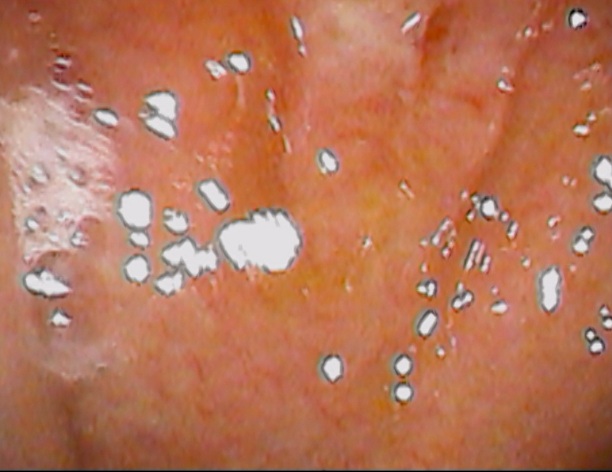

喉👄を診てみます。

ありました

この位置です↓